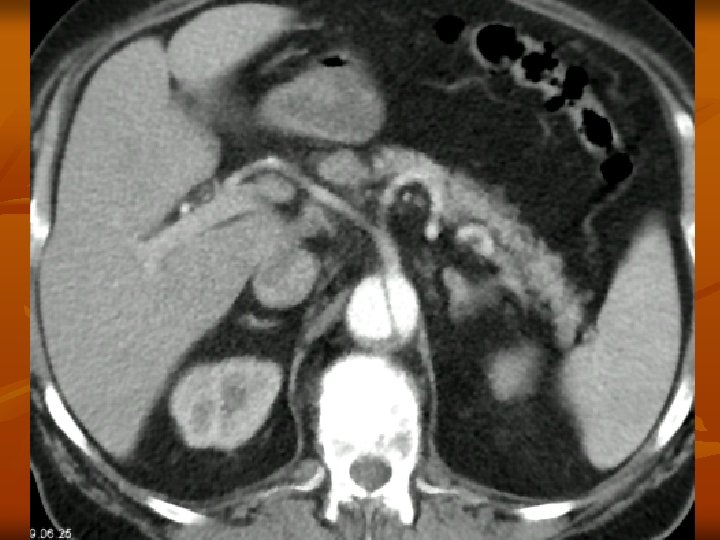

A CTA leggyakoribb alkalmazása n Mellkasi és hasi aorta, valamint iliaca rendszer vizsgálata aneurysma esetén a CTA pontos választ ad: - nagyság – növekedés - kiterjedés – kiinduló erek érintettsége - trombotizáltság - ruptura fennállása – haematoma

A CTA leggyakoribb alkalmazása dissectio esetén a CTA pontos választ ad: - dissectio fennáll vagy nem a dissectio kiterjedése, típusa kettős lumen megléte pericardium érintettsége supraaorticus ágak érintettsége visceralis ágak érintettsége ruptura occlusio esetén a CTA pontos választ ad az elzáródás helyére, collateralis keringés kialakulására, a parenchyma károsodására

A CTA leggyakoribb alkalmazása n n n Renovascularis és cerebralis vasculatura obliterativ folyamatának meghatározása Abdominalis és thoracalis daganatok műtéti eltávolítása előtt vasculatura ábrázolása Pulmonalis embolia gyanújának esetén! Első vizsgálati lépésként!